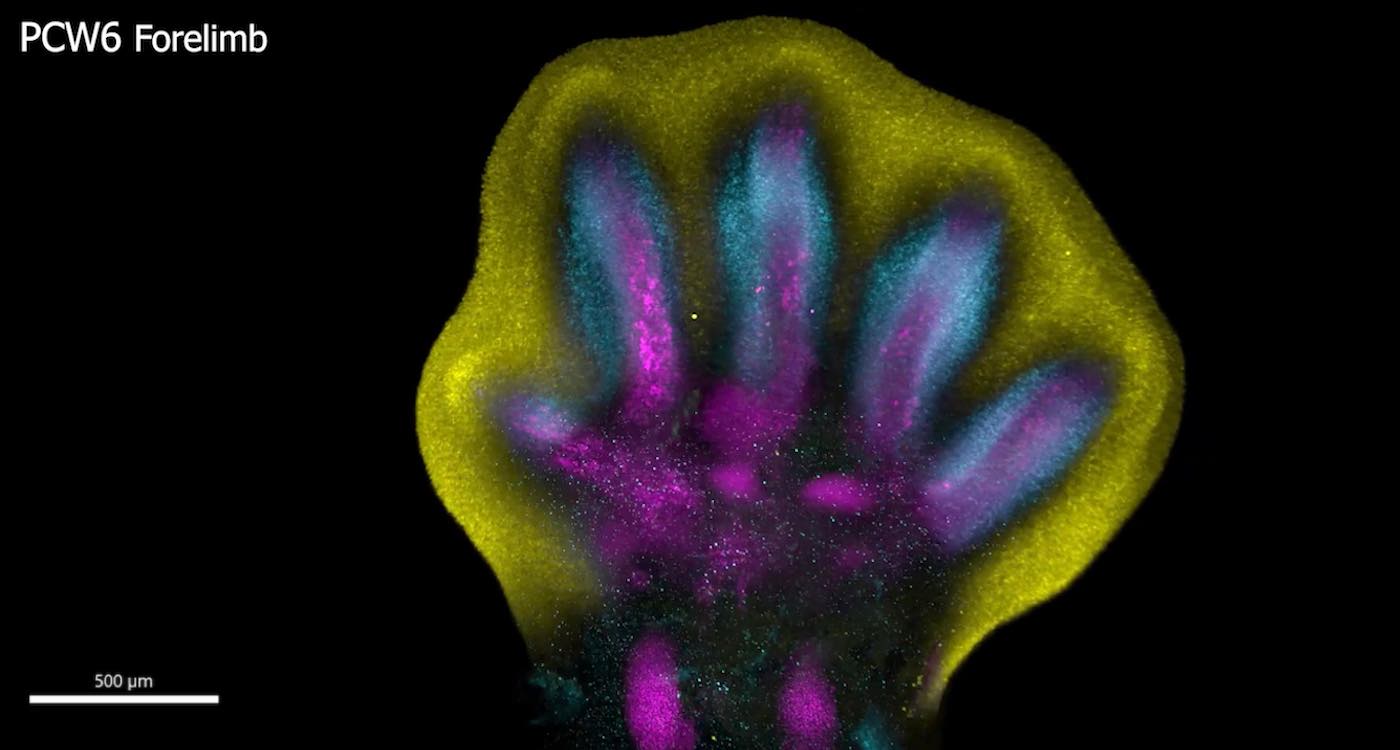

Scientists have uncovered unprecedented insights into the formation of human hands and feet and the intricate processes that govern their development.

Human fingers and toes do not grow outward; instead, they form from within a larger foundational bud, as intervening cells recede to reveal the digits beneath.

This is among many processes captured for the first time as scientists unveil a spatial cell atlas of the entire developing human limb.

Special staining of the tissue revealed clearly how cell populations differentially arrange themselves into patterns of the forming digits.

Limbs are known to initially emerge as undifferentiated cell pouches on the sides of the body, without a specific shape or function. But after 8 weeks of development, they are well differentiated, anatomically complex and immediately recognizable as limbs, complete with fingers and toes.

In this new study, scientists from the Wellcome Sanger Institute, Sun Yat-sen University, and their collaborators analyzed tissues between 5 and 9 weeks of development. This allowed them to trace specific gene expression programs, activated at certain times and in specific areas, which shape the forming limbs.